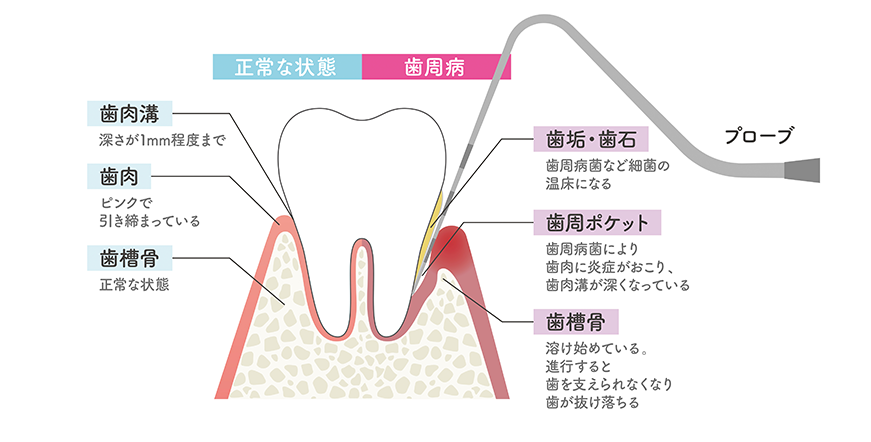

歯周病は歯茎の中に歯周病原菌と呼ばれる細菌が侵入し、徐々に増殖してその毒素が歯茎やその周りの骨を破壊してしまう病気です。

初期段階では自覚症状はほとんどなく、「歯周病かも」とご自身で気付いた時には、かなり進行した状態になっていることも少なくありません。

気になる症状がある方は早めに当院にご相談ください。

歯周病は日本人(成人)の約80%がかかっているといわれ、歯を失う原因の1位でもあります。症状は「軽度」「中度」「重度」の3段階に分類され溝の深さ(歯周ポケット)を測定することで歯周病の進行度合いを判断します。

早い段階から症状に応じた適切な治療を行うことで、歯周病の進行を防ぐことができます。

ブラッシングとスケーリングが中心となります。医院にて専用の器具で歯周ポケットに溜まったプラークや歯石を徹底的に取り除きます。ブラッシング指導を行い、患者さまが行うご自宅でのブラッシングも正しく行うことで症状の改善を目指します。

歯周病が中度まで進行すると、歯周ポケットが深くなっているためルートプレーニングという治療法が必要になります。ルートプレーニングは、スケーリングで除去しきれない歯根に付着したプラークや歯石も除去できます。

スケーリングやルートプレーニングで症状が改善されない場合、歯周組織再生という治療を行い、歯周病で溶けた骨の回復を行うなどの外科的な処置が必要になります。